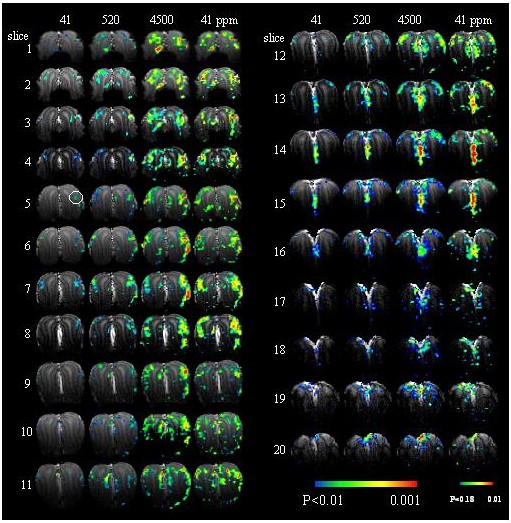

41, 520, 4500 ppm

The activity patterns for isoamyl acetate at different concentrations. The coronal slices are arranged from anterior to posterior. The intensity of the pattern is concentration-dependent (columns 1 to 3), but the overall topography of the pattern is concentration-independent (columns 3 and 4).